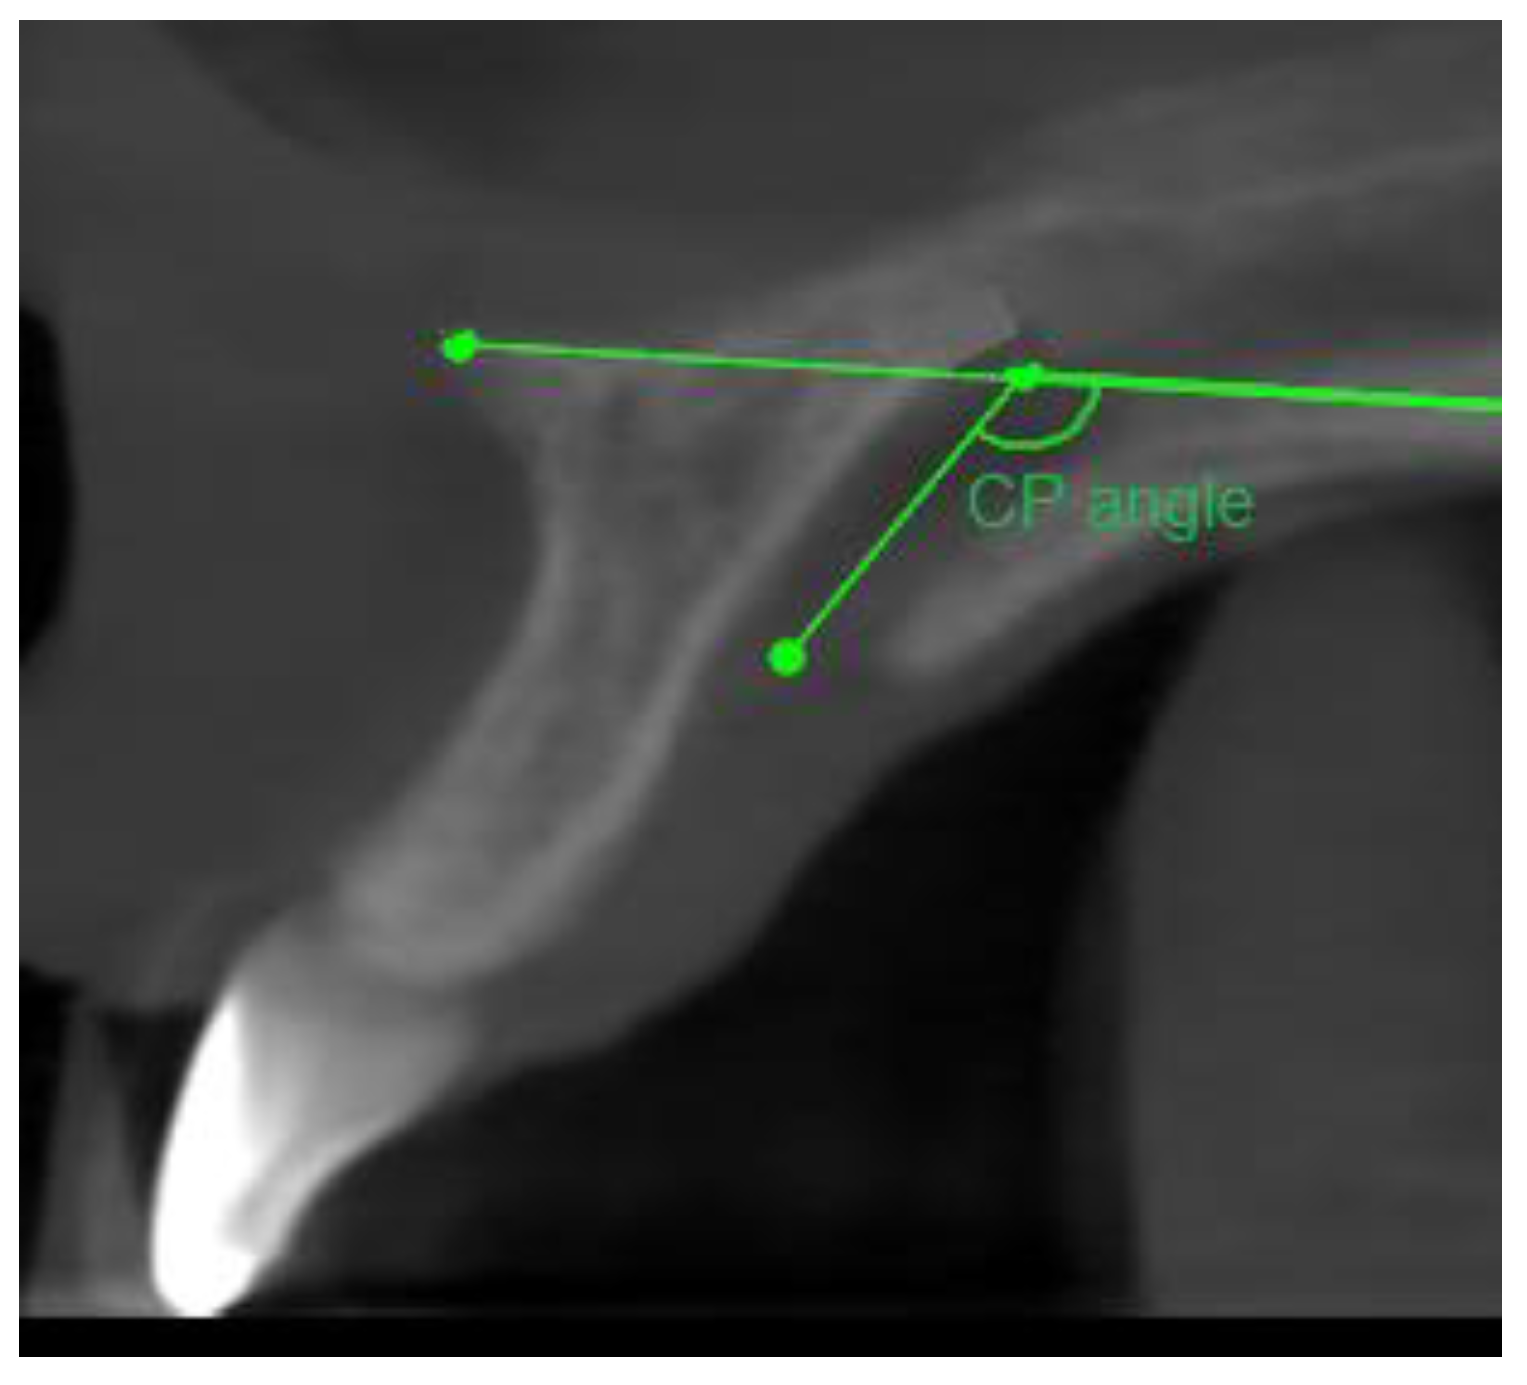

- Sagittal plane:

- Angle formed by the long axis of the incisor and the palatine plane—CP angle.